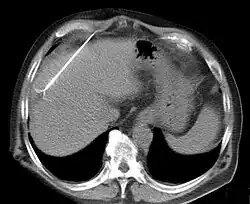

RFA may be performed to treat tumors in the lung,[9][10][11] liver,[12] kidney, and bone, as well as other body organs less commonly. Once the diagnosis of tumor is confirmed, a needle-like RFA probe is placed inside the tumor. The radiofrequency waves passing through the probe increase the temperature within tumor tissue, which results in destruction of the tumor. RFA can be used with small tumors, whether these arose within the organ (primary tumors) or spread to the organ (metastases). The suitability of RFA for a particular tumor depends on multiple factors.